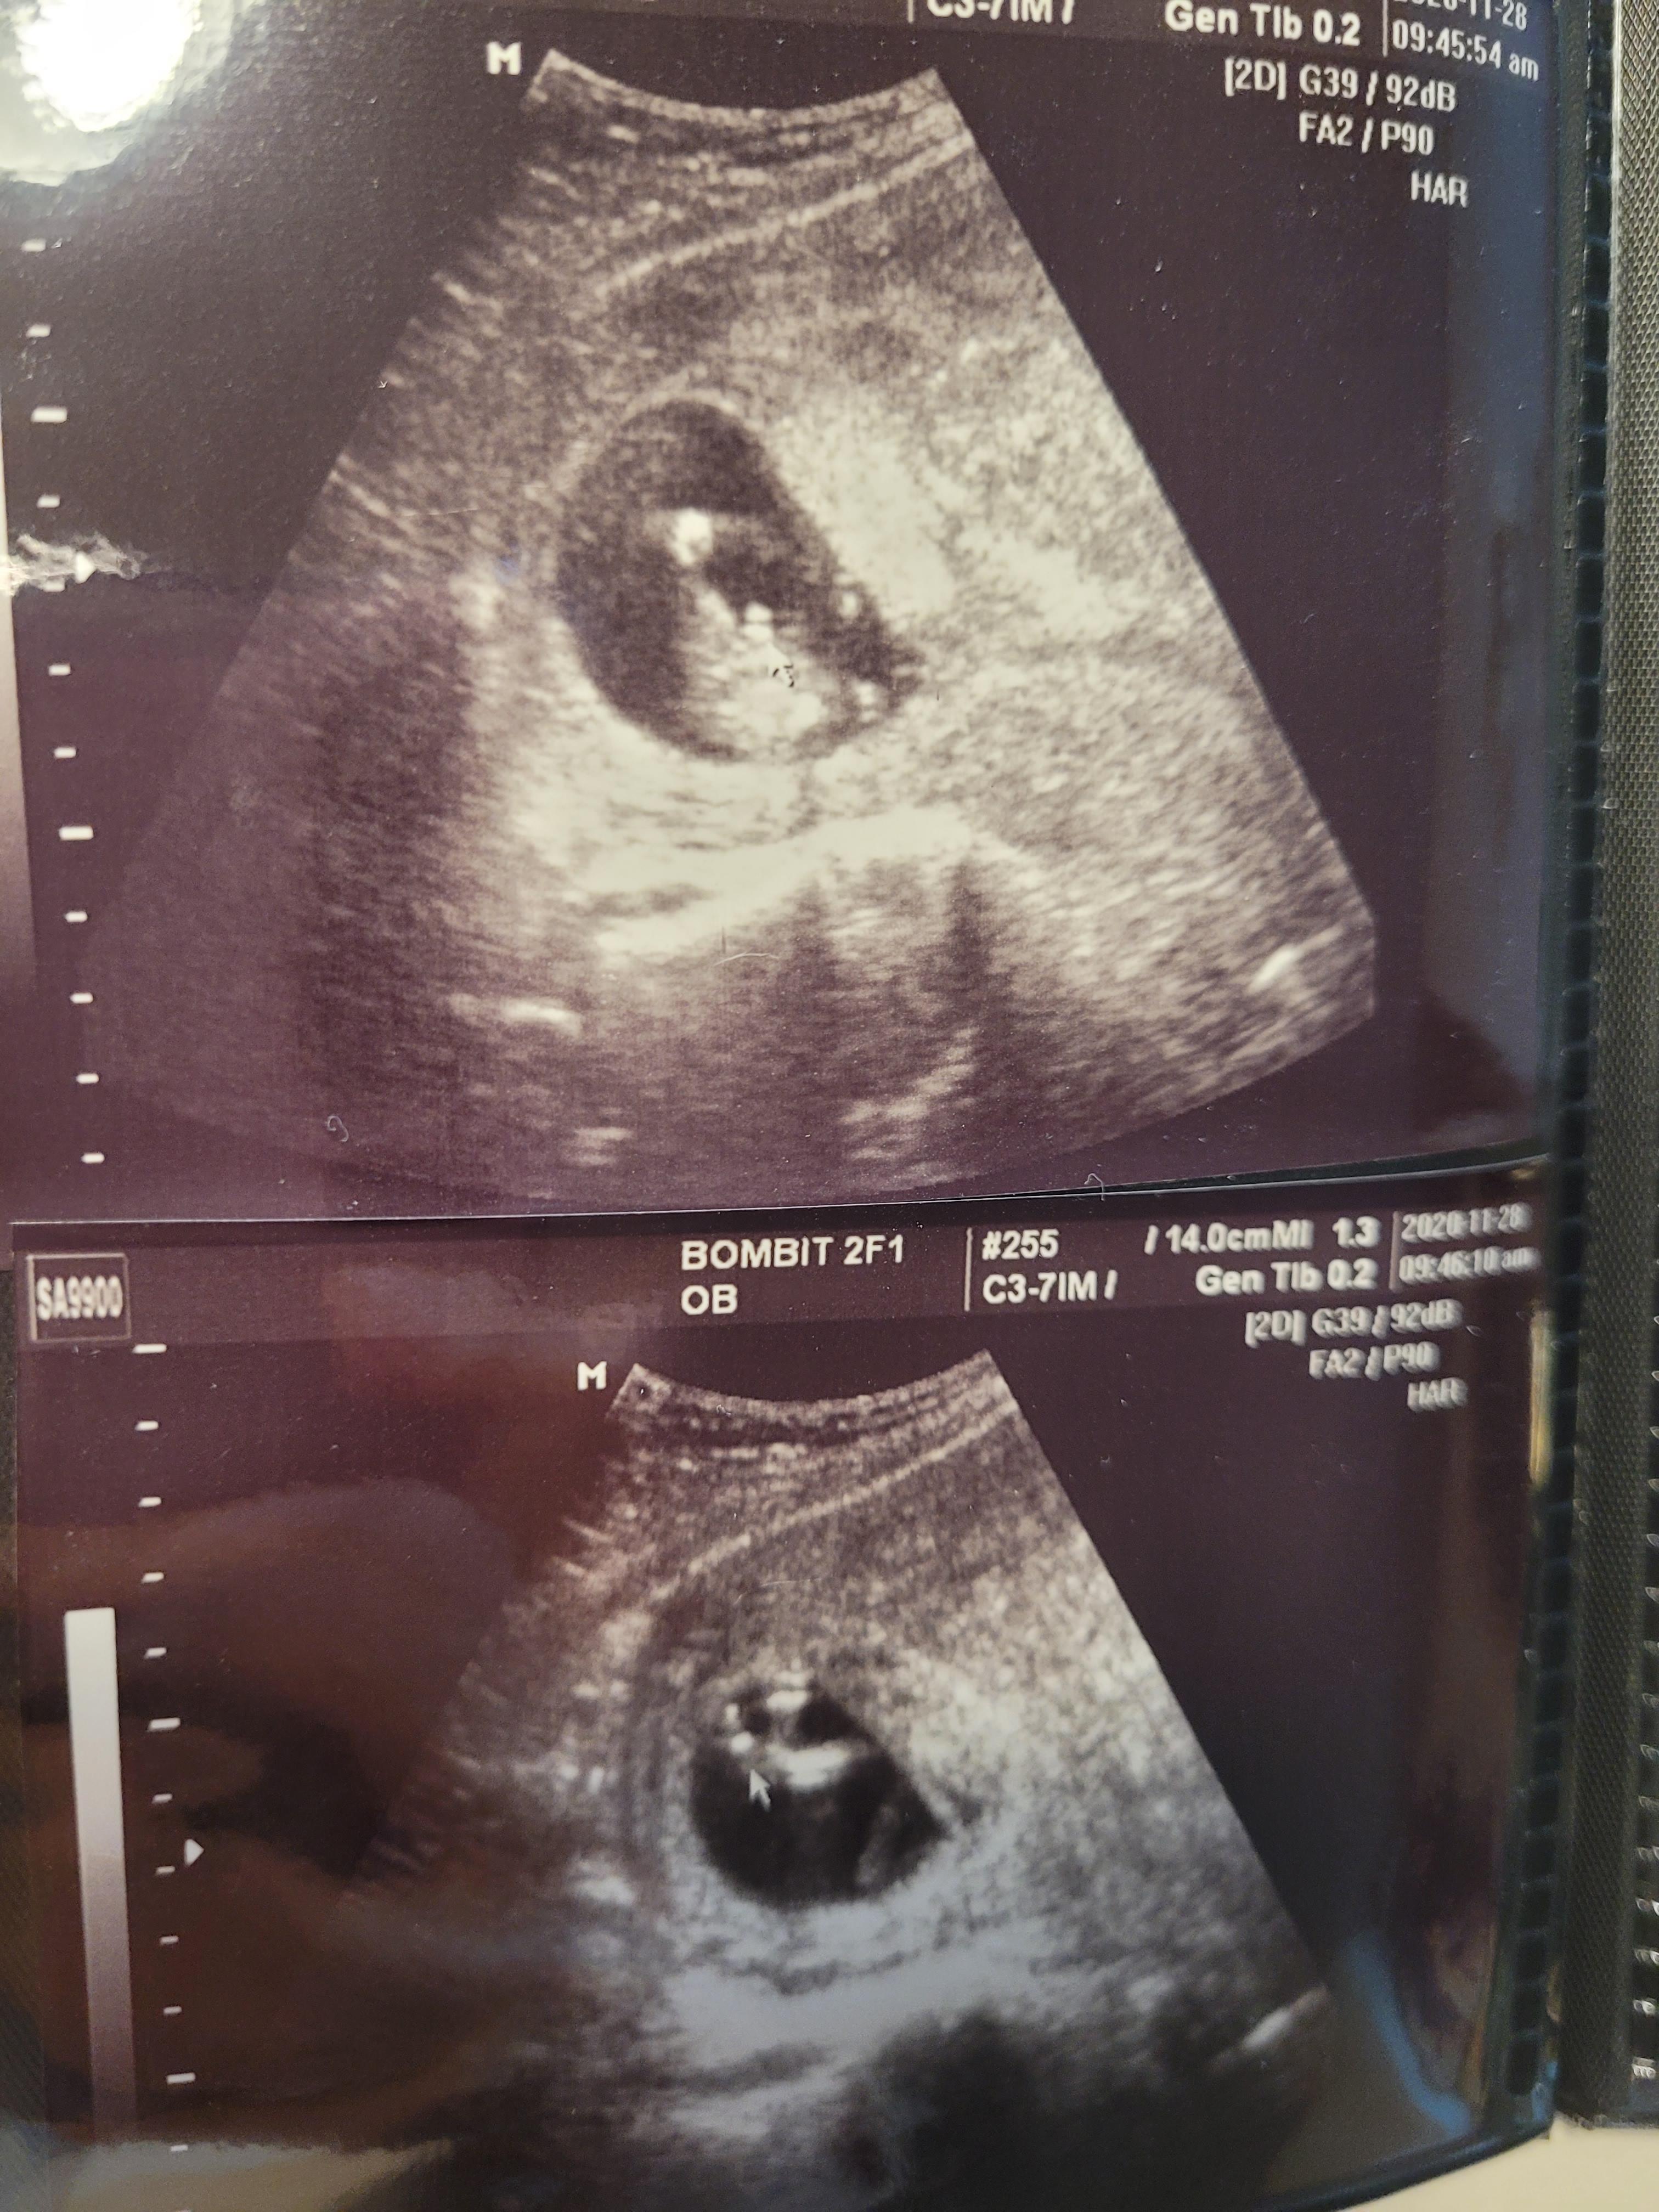

16주에 초음파로 보니 아무 이상이 없더라고요^^

뜻밖의 성별..?

지난 12주차 초음파에서 원장님이 다리사이에 뭐가 보이는것 같다고는 하셨는데 ㅎㅎ

12주엔 아기 성기가 완성되지 않을때라 명확하지않다며 16주에 다시 보자고하셨거든요.

이번 초음파를 보시더니 다리 사이에 무언가가 너무나 잘 보인다고 하시며

사진으로 캡쳐도 해주시고요ㅎㅎ

그렇게 저는 아들맘이 되었어요^^

16주까지 기다리지않고 바로 알게되서 얼떨떨하기도 했고,